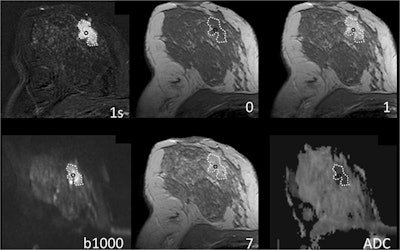

Dynamic contrast-enhanced imaging of the initial phase (IP) and delayed phase (DP) is a key part of any clinical breast MRI protocol. However, because DWI has been used increasingly as an add-on sequence, Dietzel's group sought to investigate whether it could be used instead of the delayed-phase part of the protocol.

But adding DWI plus the standard MRI protocol increases scanning time and exam complexity, the researchers explained. They theorized that because the delayed-phase curve type and the apparent diffusion coefficient (ADC) maps obtained from DWI are affected by extracellular space characteristics, perhaps the physiological and diagnostic information they glean would overlap -- thus allowing DWI to be used instead of the delayed-phase part of the MRI protocol.

The study included 132 patients with 145 lesions with equivocal or suspicious findings at ultrasound and/or mammography who underwent diagnostic breast MRI. Of these 145 lesions, 101 were malignant and 44 were benign. Dietzel's group, which included two researchers from the Medical University of Vienna, assessed three sections of the MRI protocol: the initial-phase enhancement, the delayed-phase enhancement, and the ADC maps obtained from DWI. The group examined mean region of interest values for the three sections, as well as the following multiparametric combinations: